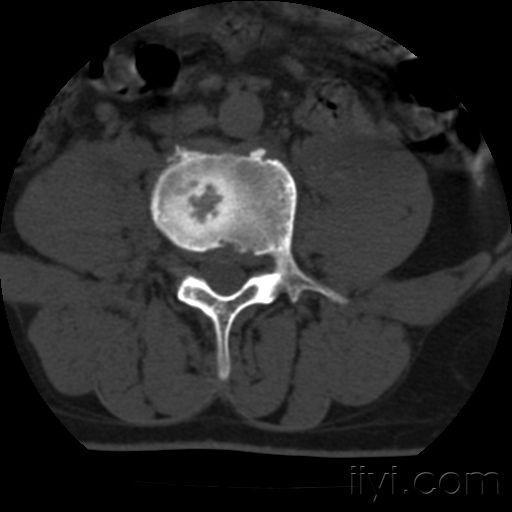

脊柱结核ct

脊柱结核ct,脊柱ct

脊柱结核

脊柱结核的ct及mri诊断影像天地